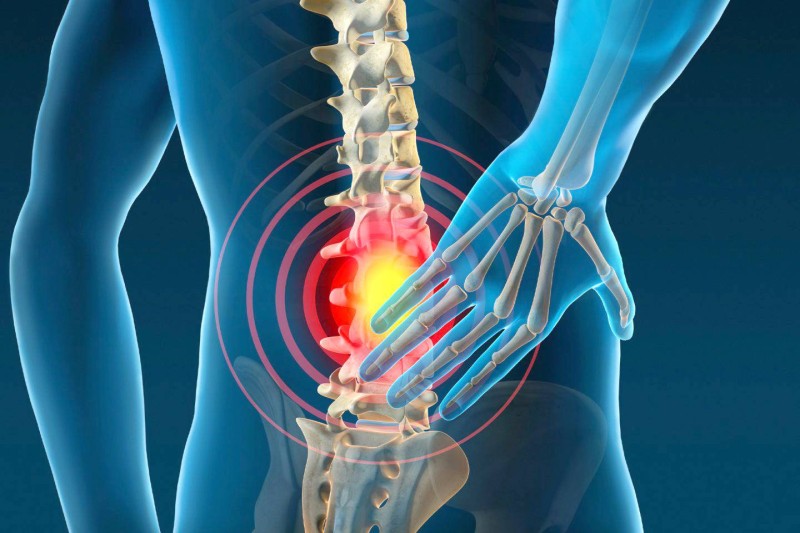

- يخفف آلام الظهر

يعمل المشي للخلف أيضا على إجبار عضلات المؤخرة على الانقباض بشكل متكرر، مما يقويها بمرور الوقت، ويُحسّن وضعية الجسم والتوازن واستقرار العمود الفقري السفلي، ويساعد في تخفيف آلام الظهر مع التقدم في العمر.